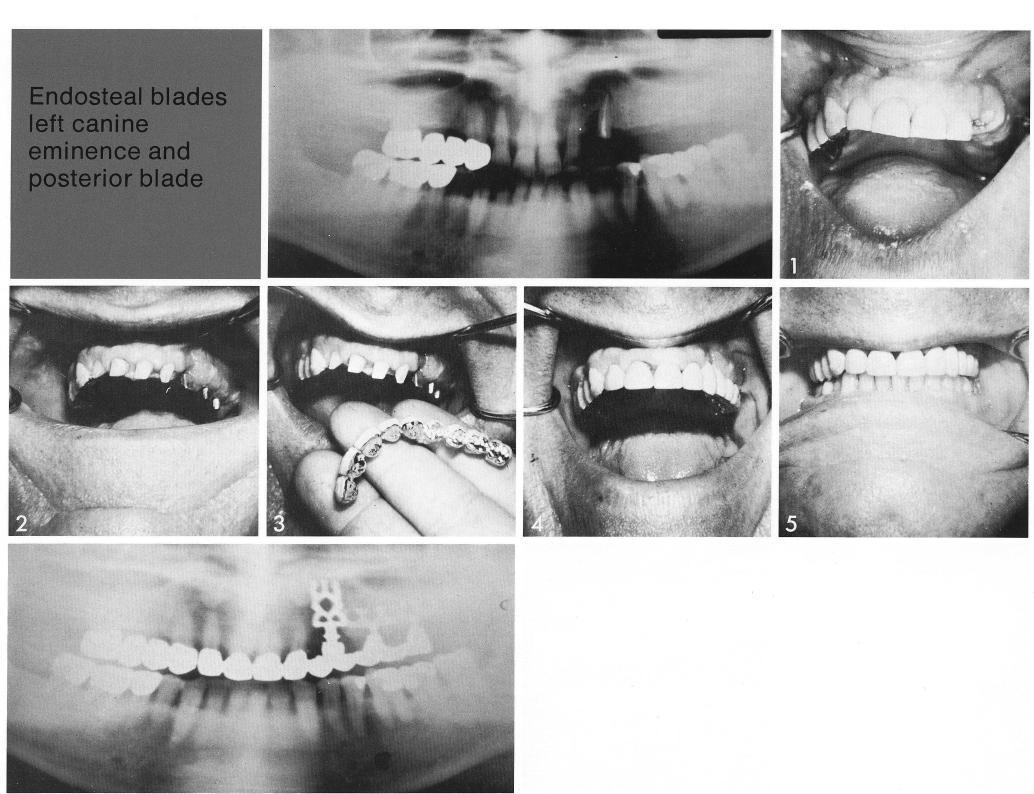

Endosteal blade

left canine eminence and posterior blade

Additional support was needed unilaterally (1) for a partial fixed restoration. This was achieved by seating a bladevent deep within the canine pillar, and a double-posted subsinus bladevent. The completed restoration was inserted over prepared natural abutments and the bladevents, greatly improving the patient's comfort and appearance.

1 Seating a maxillary bladevent implant deep within the canine pillar